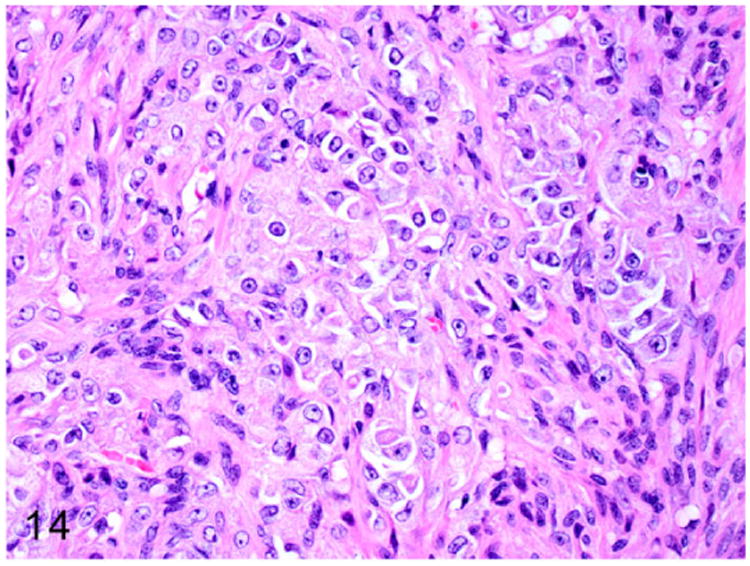

Grossly, these steroid-producing neoplasms are yellow to orange due to the intracytoplasmic lipid vacuoles.84 Histologically, the ovarian architecture is completely effaced and replaced by the lobulated expansile mass (Fig. 13). The biphasic neoplasm is predominantly composed of spindle cells and polygonal cells that are supported by dense fibrous connective tissue (Fig. 14). The spindle shaped neoplastic cells are frequently arranged in interlacing fascicles, have indistinct cell borders, moderate amount of eosinophilic cytoplasm, and elongated nuclei. The polygonal neoplastic cells are arranged in cords forming tubule-like structures, have vacuolated cytoplasm, and round to oval nuclei with prominent nucleoli. Sex-cord stromal tumors can be characterized and differentiated from smooth muscle neoplasms based on their positive immunoreactivity to markers such as calretinin and inhibin-α.

Figure 14.

Higher magnification of Fig. 13. The biphasic neoplasm is composed of interlacing streams and bundles of spindle cells and polygonal cells arranged in cords. HE.